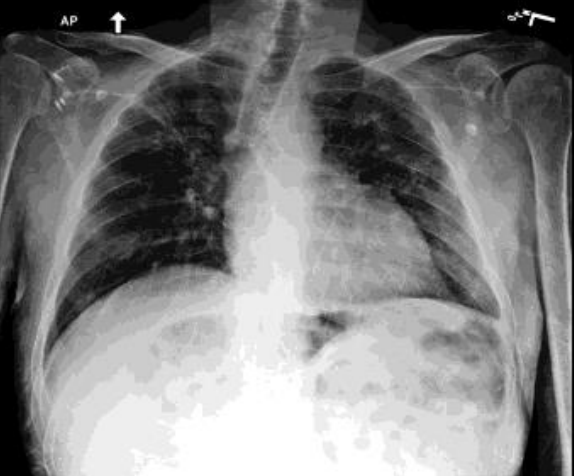

Incorrect visual understanding [Uncaptioned image] Which of the biggest in this image, lung, liver or heart? In this image, the biggest organ is the heart. In this image, the lung appears to be the biggest.

Chain-of-Medical-Thought (CoMT) in Medical Report Generation. Refer to caption Medical Report: AP and lateral views of the chest were provided in the X-ray. Lung volumes are low. There are findings consistent with chronic lung disease such as sarcoidosis. Prominence of the pulmonary interstitial markings is due to mild heart failure. There is no pleural effusion or pneumothorax. The size of the heart is normal. The cardiomediastinal silhouette is notable for a tortuous aorta. Bones are slightly osteopenic. The impression suggests that 1. Improving right upper lobe consolidation; 2. Mild heart failure; 3. Findings of chronic lung disease, most likely sarcoidosis. Construction of Hierarchical QA pair Q1: What modality is used to take this image? A1: The modality used for this image is an x-ray. Q2: What organs are in the image? A2: The x-ray image depicts the heart and lungs. Q3: Describe the size of the organ in the image. A3: The size of the heart is normal. Lung volumes are low. Q4: Where are the abnormalities in the organs? A4: Right upper lobe consolidation Q5: What symptoms are shown in this image? A5: Prominence of the pulmonary interstitial markings. …. Q6: Describe the patient’s health condition according to this image. A6: The overall impression from the x-ray is… Chain-based QA Pair Refactoring Q1: What modality is used to take this image? Q2: The modality used for this image is an xray. So, What organs are in the image? Q3: The modality… The x-ray image depicts the heart and lungs. Describe the size of the organ in the image. Q4: The modality… The x-ray image depicts … The size of the …. So, Where are the abnormalities in the organs? Q5: The modality… The x-ray image… The size…. Image shows right upper lobe consolidation. So, what symptoms are shown in this image? Q6: The modality… The x-ray image… The size…. Image shows right upper lobe consolidation. The image shows prominence of …. Describe the patient’s health condition according to this image. High Quality Report

Figure 3: Illustration of CoMT’s process for constructing hierarchical QA pairs based on real clinical image reports. This example is from the original paper [87].